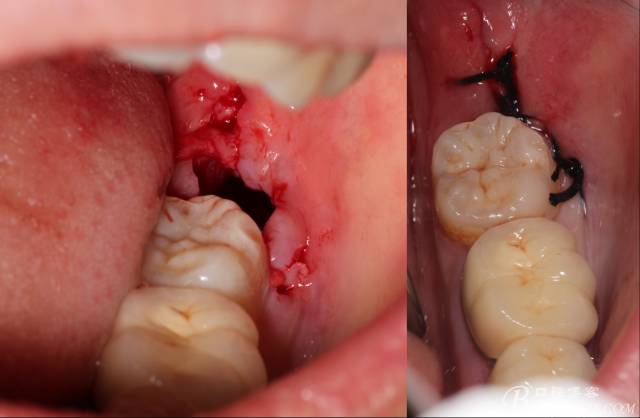

切開(kāi):角形切口,這個(gè)位置切開(kāi)我喜歡更易操作12#刀。

鈍性翻辨露冠

角度鍋輪機(jī)結(jié)合冷鹽水冷卻分冠

分冠完成

取出阻力部分冠

在取出阻力冠后,嘗試性看能取出全部的牙體不,就是取不出也能整體撬動(dòng)牙根。

計(jì)劃總趕不上變化,何況是充滿變異的智齒。由于可操作空間較小,原來(lái)計(jì)劃?rùn)M向分根改成矢狀分根。

現(xiàn)在都在提倡微創(chuàng),個(gè)人看法微創(chuàng)是相對(duì),所當(dāng)然微創(chuàng)是我們的追求。完全撥出,縫合關(guān)閉創(chuàng)口,常規(guī)智齒撥除醫(yī)囑,不適隨診。